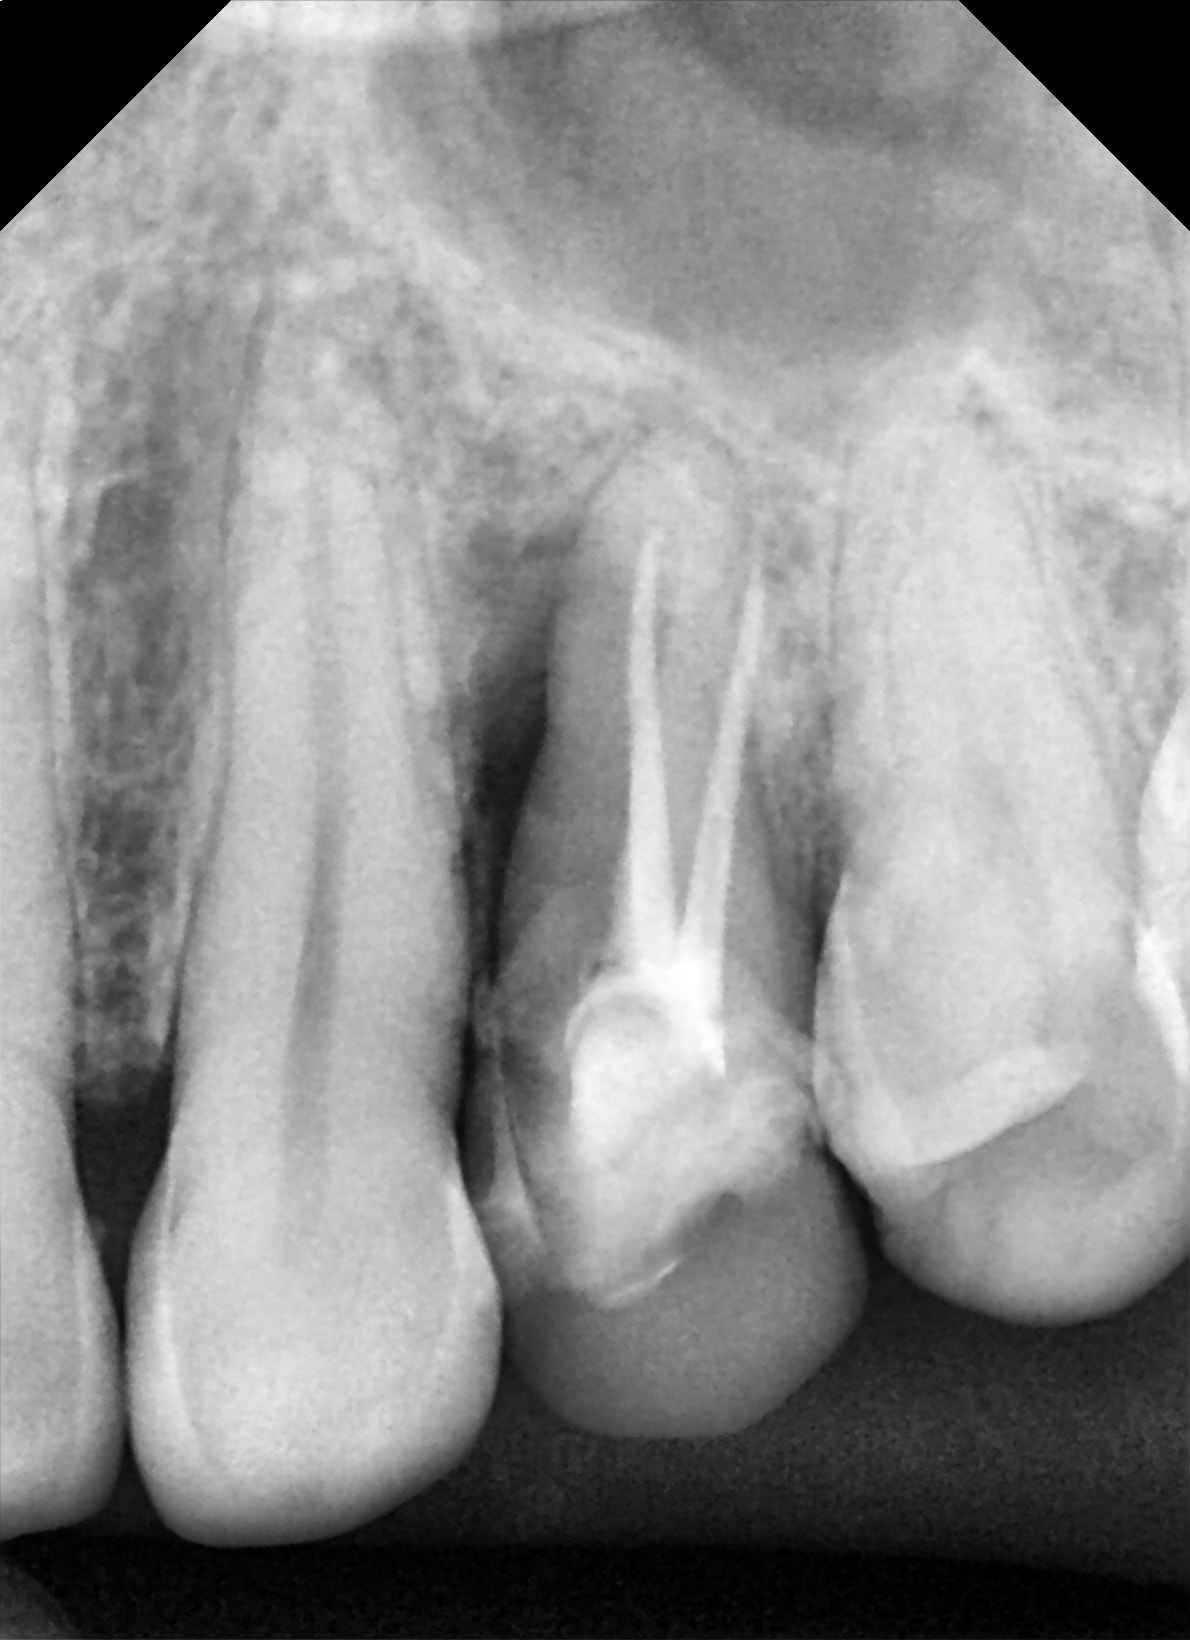

Effectivement première fois que cela m'arrive en 35 ans d'exercice !!

Traitement canalaire de la 47: la pâte à canaux ( Sealite Ultra ) a fusé au dela de l'apex lors de l'obturation à la guttachaude. Malheureusement le canal dentaire passe juste au niveau de l'apex et la pâte est rentré à l'intérieur.

La patiente n'a eu aucun signe pendant 3 jours puis paresthésie au niveau mentonnier ( pas au niveau labial) . La patiente décrit cela comme une fin d'anesthésie.

Quelles sont vos avis sur la récupération de la sensibilité ?

Depuis 3 semaines la paresthésie n'a pas changé ( diminué ou augmenté) .

19/01/2020 à 19h24

Désolé pour les images cone beam: je n'arrive pas à les mettre dans le bon sens!!